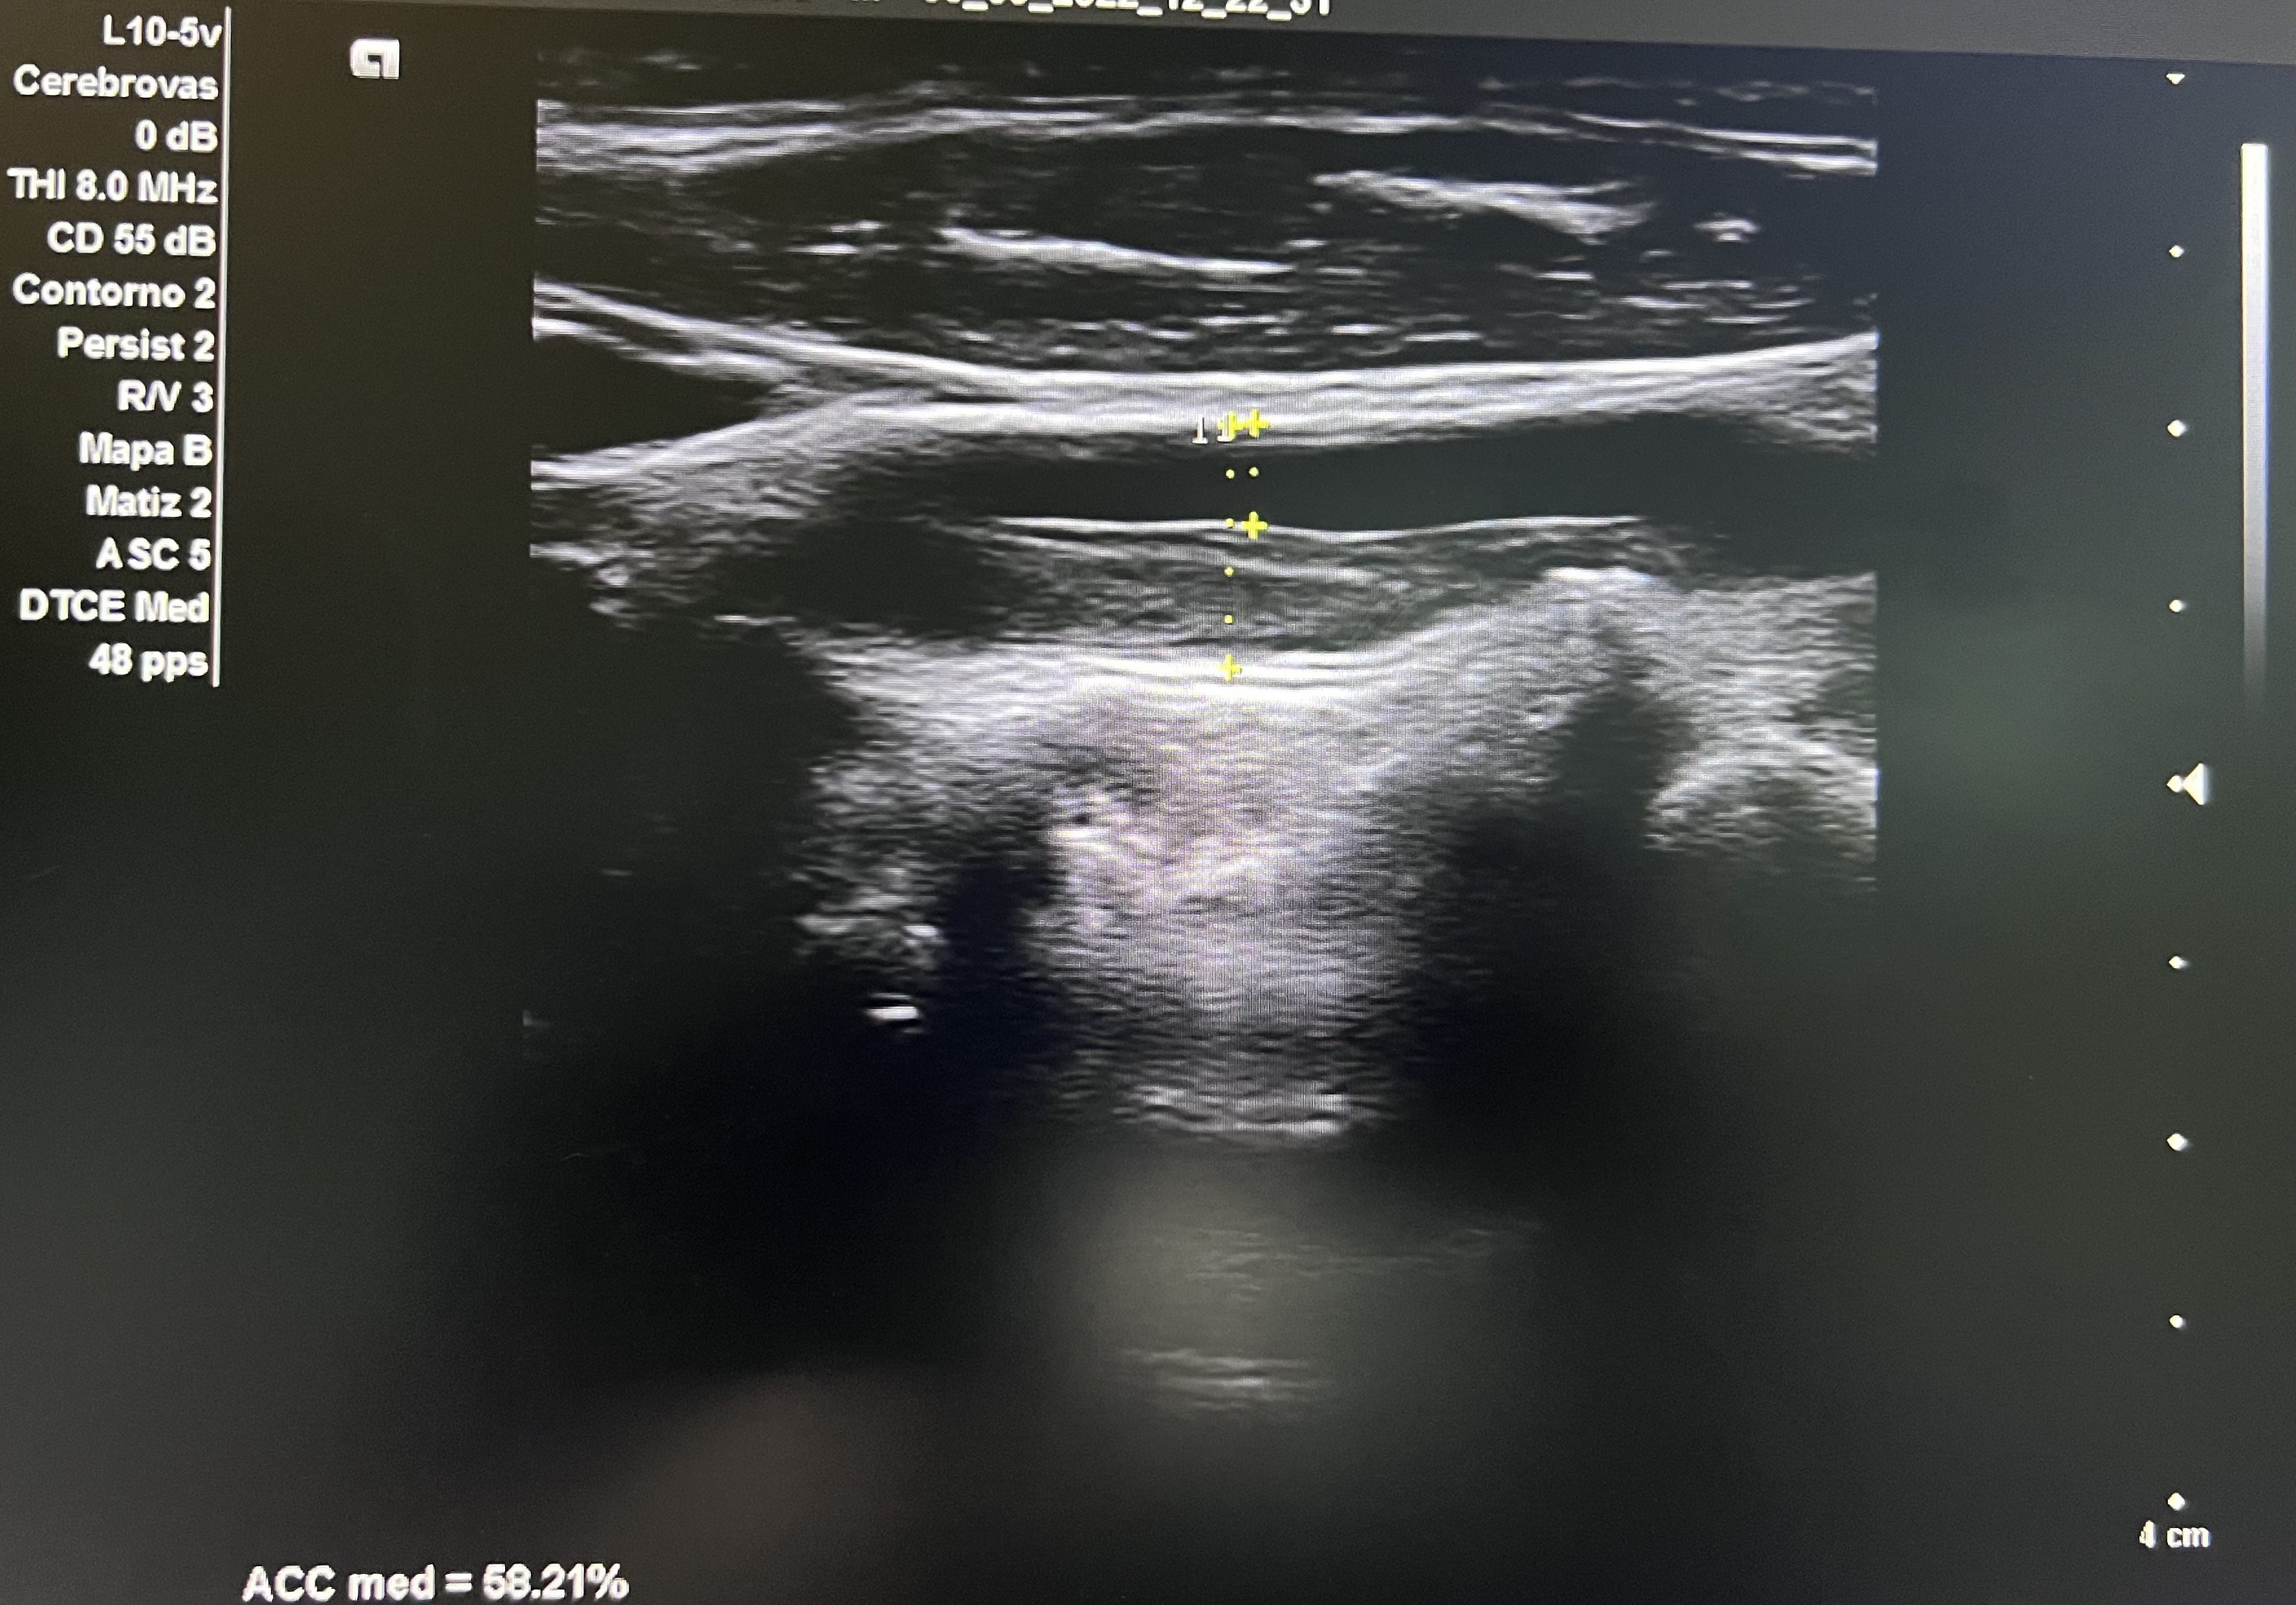

Aorta abdominal de calibre normal. Arteria carótida derecha sin lesiones. En arteria carótida común izquierda se observa placa longitudinal desde porción media hasta proximal que obstruye un 58% en su diámetro máximo.